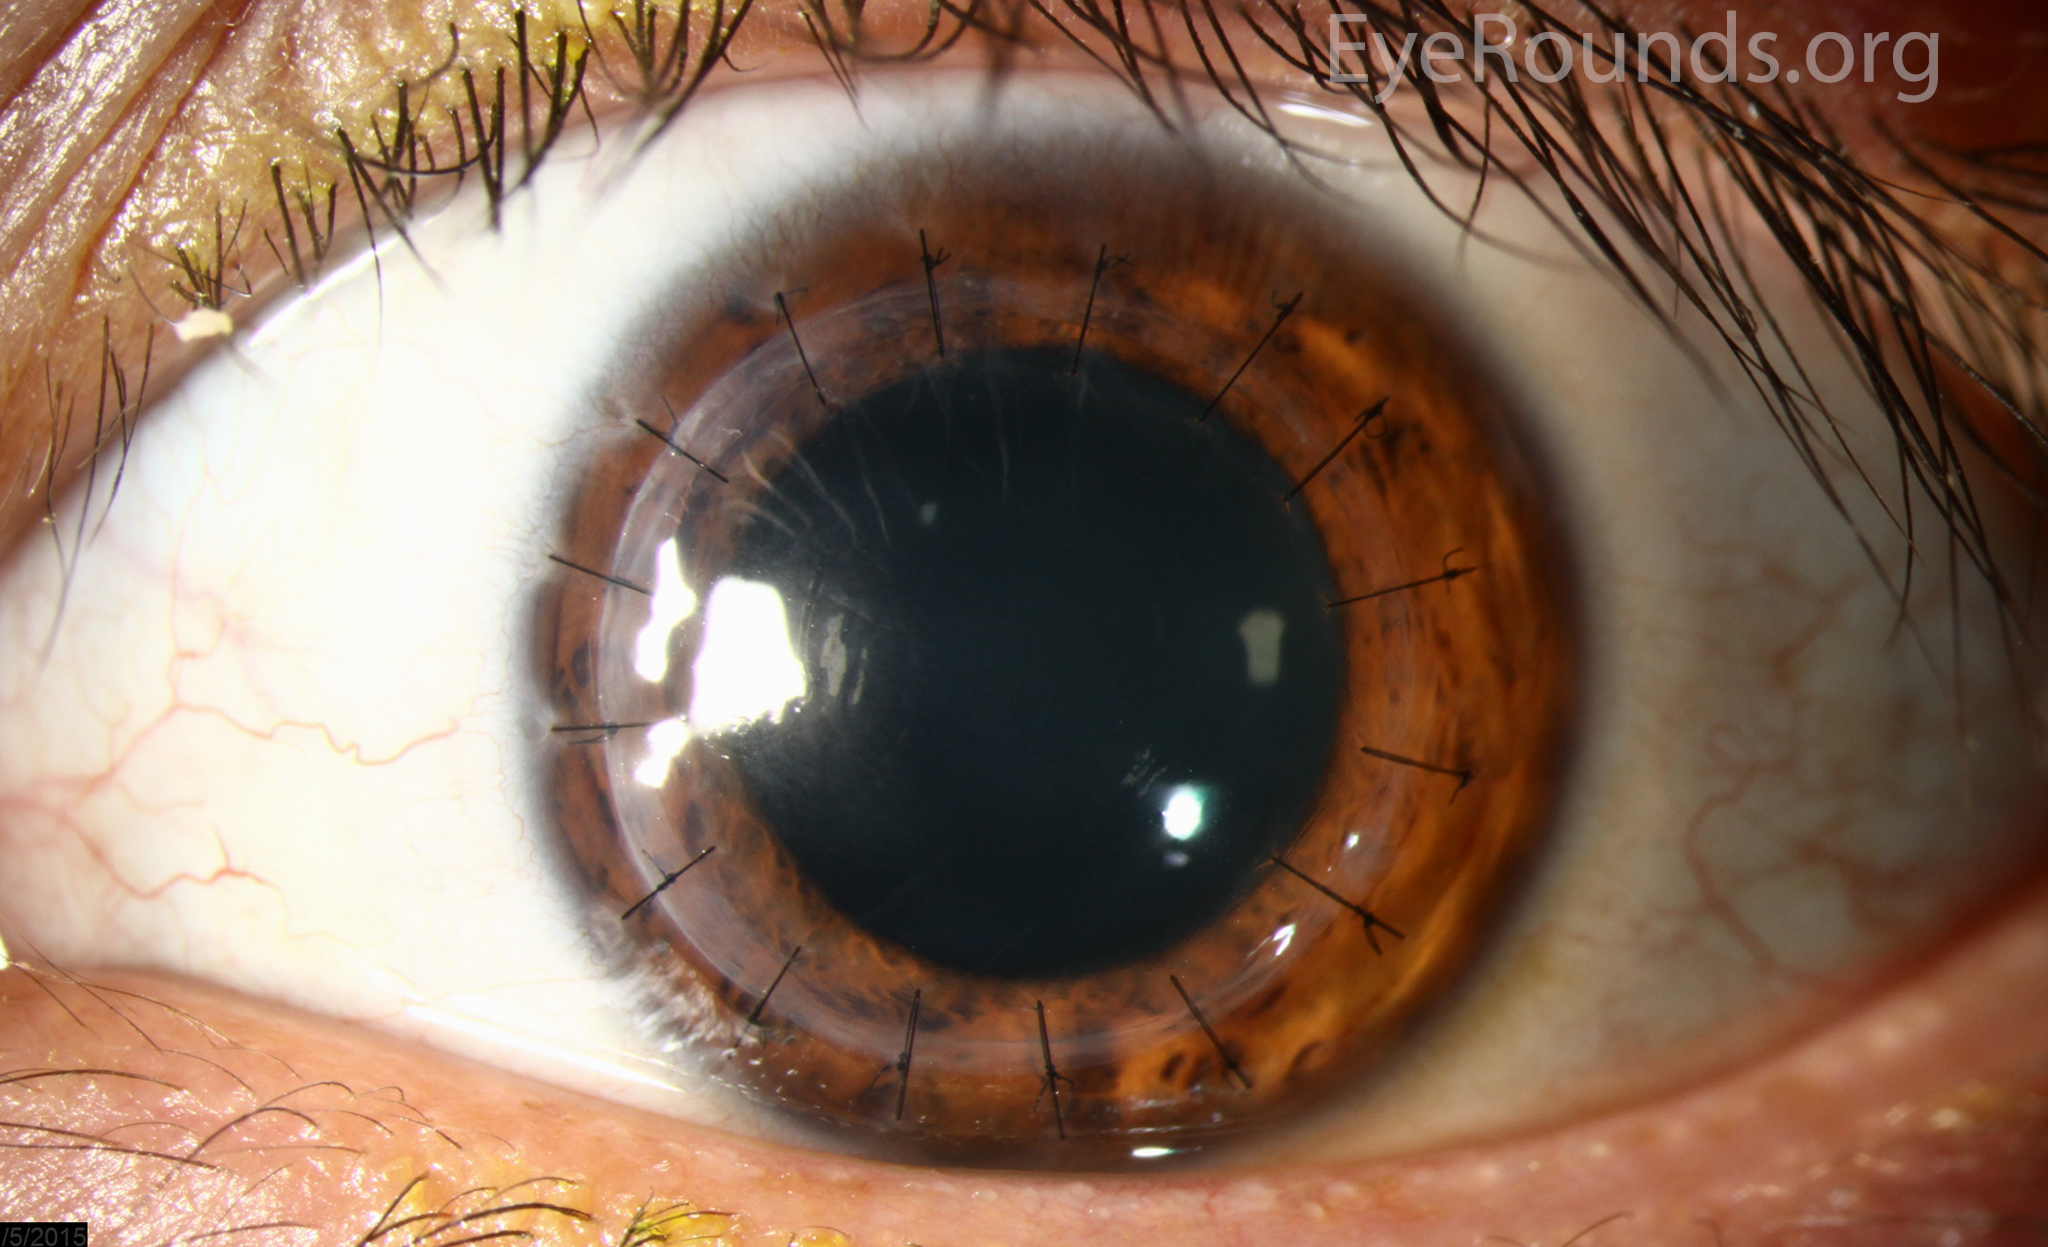

PK is a full-thickness transplant procedure, in which a trephine of an appropriate diameter is used to make a full-thickness resection of the patient's cornea, followed by placement of a full-thickness donor corneal graft. Interrupted and/or running sutures are placed in radial fashion at equal tension to minimize post-operative astigmatism (Figure 2). Later, the sutures are removed selectively to reduce the amount of astigmatism present. A transplant can last decades with proper care (Figure 3). While once the most prominent type of corneal transplant, PK has been supplanted by partial thickness techniques for endothelial dysfunction without significant stromal scarring. PKs are performed primarily for visually significant stromal scarring, opacities with an uncertain status of the endothelium or significant posterior corneal involvement, corneal ectasia (such as keratoconus and pellucid marginal degeneration, especially if there is history of hydrops), combined stromal and epithelial disease (such as Peters anomaly), and infectious or non-infectious corneal ulcerations or perforations (1, 14). A variant of the procedure, the mini-PK, can be used to treat more focal defects in the cornea (Figure 4).